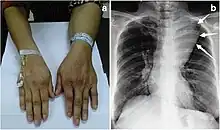

Angiolipoma is a subcutaneous nodule with vascular structure, having all other features of a typical lipoma. They are commonly painful.[1]: 624 [2] Angiolipomas manifest as multiple painful subcutaneous nodules commonly on the upper limbs. The can occur sporadically, with a family history or after trauma. Angiolipomas can be seen on CT scans and MRI but are diagnosed based of histopathology. Total excision or liposuction is used to treat angiolipomas. They are more common in men and usually appear in third and second decades of life.

Angiolipoma typically manifests as many, painful subcutaneous nodules (solitary in only one-third of patients), most commonly originating in the upper limbs (of which the forearm accounts for around two thirds), trunk, and lower limbs.[3][4] These lesions are well-defined, usually measuring less than 4 cm.[5]